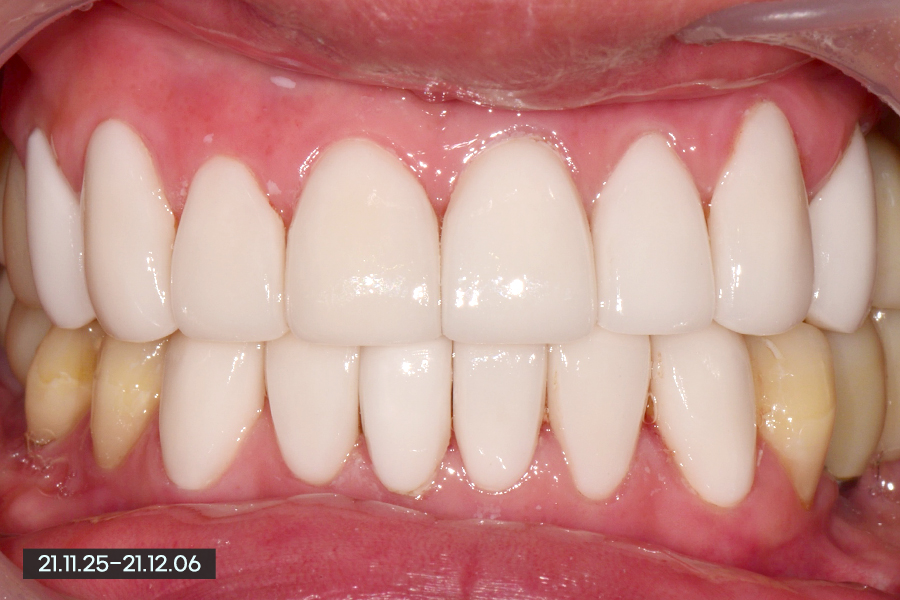

저희가 보여드리는 색상 가이드 중 BL2라는 색상인데 요즘 여성분들이 많이 하시는 색상 중에서도 밝은 색상에 속하지만 환자분께서는 밝은 치아를 원하셨습니다.

뒷 부분에 있는 어금니 쪽의 임플란트를 제외하고 전체를 다 진행하였고, 환자분께서 이렇게 밝은 색상을 원하셔서 마무리를 하였습니다.

실제로 환자분들과 상담시 사진을 보시면 '왜 이렇게 밝게 했나요?'라고 물어보시는 경우가 있는데, 화면이 밝게 나와서 좀 더 밝아보기에 나오기도 했지만 실제로 얼굴과 함께 보면 어색하지 않아 환자분의 만족도가 높았습니다.